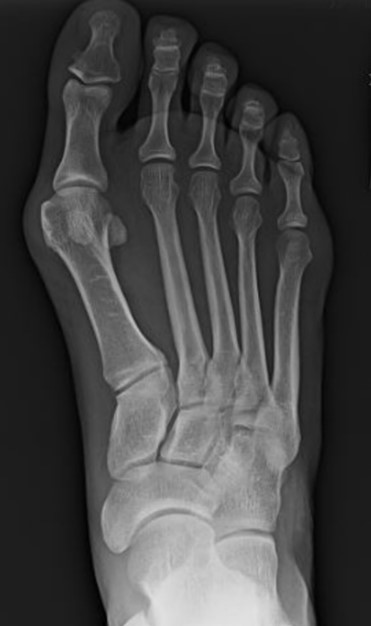

pre-operative weightbearing radiographs bunion deformity

Figure 2: pre-operative weight-bearing radiographs, bunion deformity